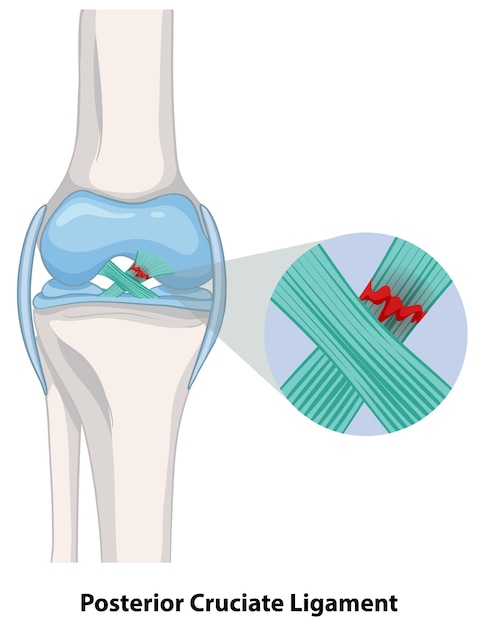

Le ligament croisé antérieur (LCA) est une des structures clés garantissant la stabilité genou lors des activités sportives. Au football, la fréquence des contacts, les accélérations brutales et la nécessité de pivoter rapidement exposent particulièrement ce ligament aux contraintes mécaniques sévères. L’une des causes principales de blessure au football reste l’entorse genou, souvent accompagnée d’une déchirure partielle ou complète du ligament croisé.

Les mécanismes traumatiques typiques incluent un changement rapide d’appui ou un choc latéral, induisant une torsion anormale du genou. Ces mouvements sont fréquents lors des phases d’accélération ou de duel pour la possession du ballon. La nature multifactorielle des facteurs de risque comprend notamment des éléments biomécaniques, l’asymétrie musculaire, la fatigue et un manque de préparation adéquate. Par exemple, une insuffisance de renforcement musculaire peut diminuer la protection naturelle de l’articulation et augmenter la probabilité d’entorse.

De plus, certains profils comme les joueuses féminines sont statistiquement plus sujets à ces blessures, en raison notamment de différences anatomiques et hormonales affectant notamment la laxité ligamentaire. La répétition des microtraumatismes et l’absence de récupération complète peuvent aussi fragiliser le ligament au fil du temps. Une identification précoce des signes cliniques comme une douleur intense, un gonflement rapide ou une sensation d’instabilité doit immédiatement orienter vers un diagnostic médical approfondi, incluant un examen clinique et souvent une IRM, référence pour vérifier un état normal des genoux ou la présence de lésions.

Pour illustrer, lors d’un match de championnat, un joueur qui effectue un changement rapide de direction en pivotant sur un pied peut brusquement ressentir une décharge douloureuse suivie d’une sensation d’instabilité, signe évocateur d’une blessure sévère au ligament croisé. Cette situation requiert une prise en charge rapide pour limiter les dégâts articulaires et optimiser la récupération. L’évaluation précise des risques dans chaque phase de jeu contribue à mieux concevoir les programmes de prévention adaptés aux entraînements et matchs.